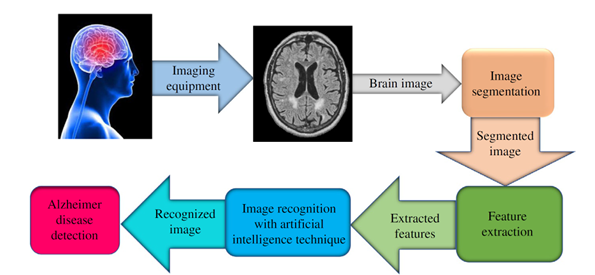

In epilepsy care, deep learning methods have made it possible to predict seizures as early as one hour before they occur, achieving prediction accuracies of up to 99.6%. Such breakthroughs hold the potential to improve safety and quality of life for millions of patients living with epilepsy.

Figure 2 Brain states in a typical epileptic EEG recording.